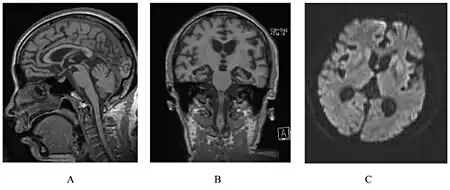

| a) Examination of the brain showing cortical brain atrophy b) coronal slide demonstrating severe cortical and subcortical atrophy c,d) microscopic anatomopathological analysis of the brain | |

A person with inherited prion disease has cerebellar atrophy. This is quite typical of GSS. GSS can be identified through genetic testing.[9] Testing for GSS involves a blood and DNA examination in order to attempt to detect the mutated gene at certain codons. If the genetic mutation is present, the patient will eventually develop GSS.